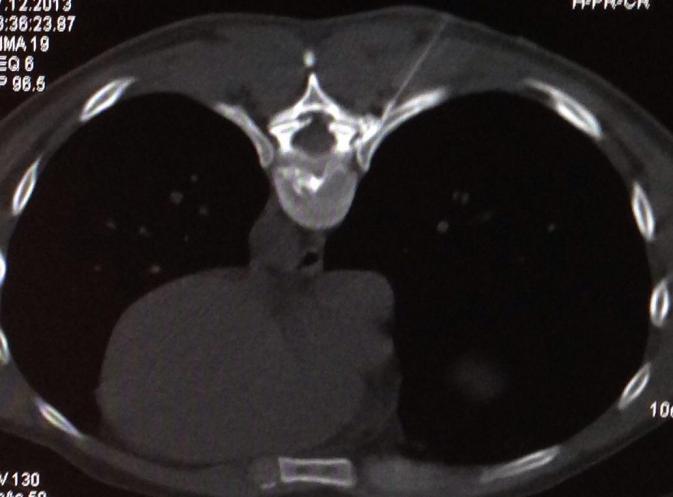

Wie immer in der Medizin ist die richtige Indikationsstellung wichtig für gute Ergebnisse. Nicht jeder Bandscheibenvorfall kann gelasert werden. So sollte der Faserring der Bandscheibe erhalten sein.